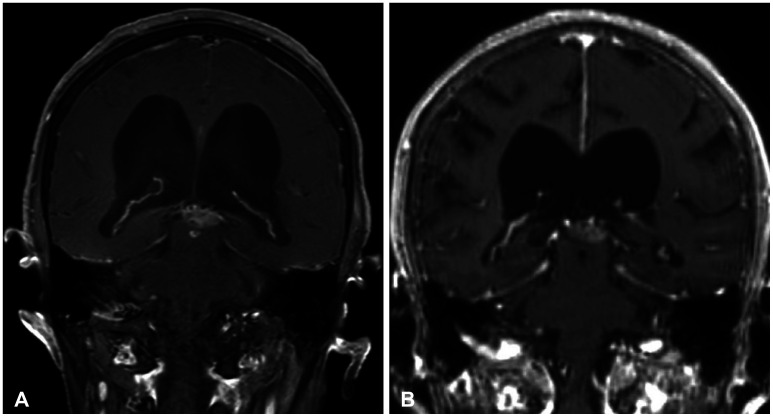

Abstract Image